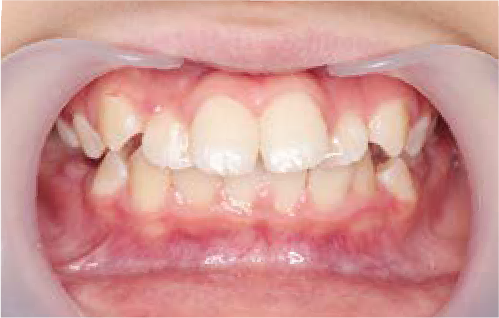

Before

After

上あごの成長が少なく、特に前歯のガタガタが目立っていました。口呼吸のクセや飲み込み方に良くないクセが確認されました。

治療を終えて

マイオブレイスとBB1装置で上あごの成長を助け、鼻呼吸や正しい飲み込み方を身につけることで、きれいな歯並びとしっかり噛めるお口に変わっていきました。

姿勢やお口の機能を正しく整えたので、後戻りしない綺麗な歯並びを維持できています。もちろん非抜歯です。

主訴・治療内容 当院と交流のある歯科医師の先生が、ご自身のお子さまの治療を任せてくださいました。

「難しい歯並びでも永久歯を抜かず、全身の健康と顔立ちも考えて治療してくれる」と信頼していただいて治療開始。

治療期間 3年

費用 462,000円(税込)